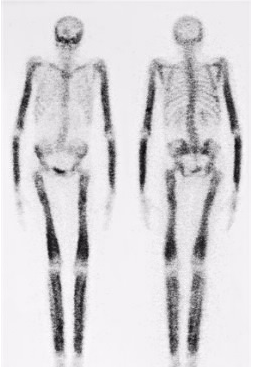

医学同位素是用于诊断和治疗各种疾病的微量放射性物质。注入到体内的同位素可以使医生确定心脏是否有足够的血流。

癌症已经扩散到病人的骨头;并帮助诊断胆囊,肾脏和脑部疾病。同位素进入恶性肿瘤后,可以杀死癌细胞,从而最大程度地减少对附近健康组织的损害。